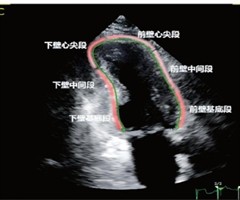

收缩后收缩参数联合定量血流比率预测ST段抬高型 心肌梗死患者PCI术预后的临床价值

摘要目的探讨收缩后收缩(PSS)参数联合定量血流比率(QFR)预测ST段抬高型心肌梗死(STEMI)患者经皮冠状动脉介入治疗(PCI)术预后的临床价值。方法收集我院行PCI的STEMI患者104例,术后 24~48h 均行二维斑点追踪超声心...